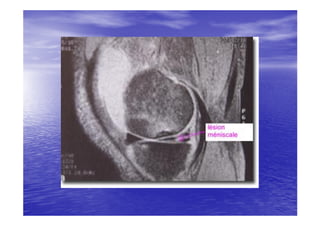

RADIO-

RADIO-ANATOMIE

• Le genou peut être exploré par les incidences

radiologiques suivantes:

– La radiographie standard de genou face/profil

– Arthrographie grâce à l'injection à l'intérieur de la

cavité articulaire du genou d'un produit de contraste

radio-opaque , on peut étudier l’épaisseur des

cartilages articulaires , les ligaments croisés , surtout

les ménisques.

– Arthrographie et scanner.

– IRM.est un excellent moyen d'étudier les ménisques ,

les ligaments , les cavités articulaires et les éléments

squelettiques.